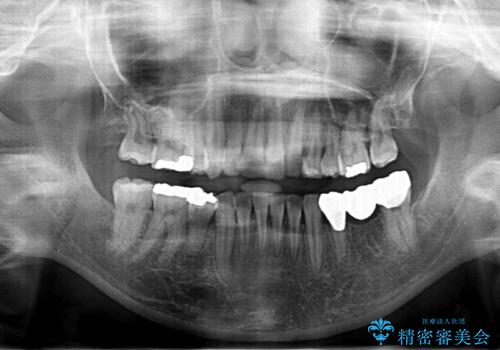

- 前歯のがたつきを主訴に来院されました。

小さいころ下の小臼歯を2本抜いたとのことでした。

上の歯を2本抜歯して矯正しています。

また、右上の7番(一番後ろの歯)の状態が悪く、根尖病変がありました。根の治療をする選択肢もありましたが、歯質も薄く、予算的にも治療が難しかったため、抜歯して親知らずを並べています。

左下6番(後ろから2番目の歯)も状態が悪かったため抜歯してブリッジにしています。

矯正治療をしたことで根の向きが治り、神経を取らずにブリッジにすることができました。